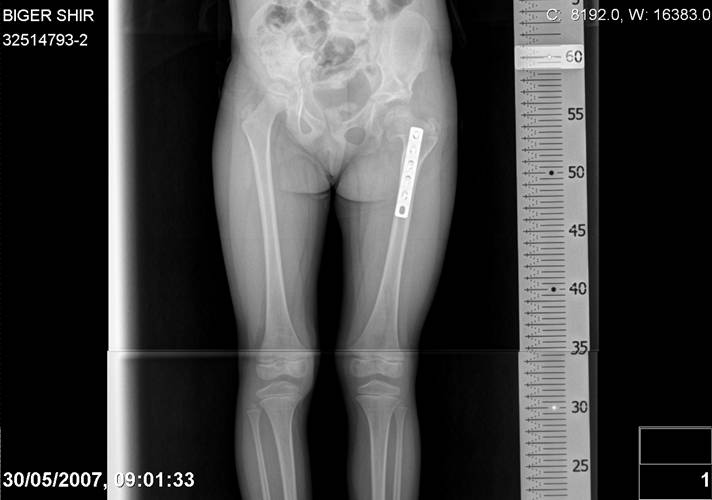

Здравствуйте, уважаемые коллеги.Обратилась девочка 6-ти лет из жалобами на боль в левом т/б суставе,хромоту Из анамнеза : ребенок лечился с рождения по поводу врожденного вывиха бедер. В возрасте 3- х лет в одной из клиник была выполнена остеотомия таза по Пембертону и варизирующая остеотомия бедра слева, справа - остеотомия таза по Солтеру и остеотомия бедра. Посоветуйте тактику лечения. С уважением Ihor

Smotritsya parshivo konechno(pseudoacetabulum,partial AVN), no v6 let ya by popytalsya ispravit chto moghno:shortening (ne boyatsya ubrat bolshoi fragment),derotation(30 gradusov ne bolshe)+pelvic osteotomy in true acetabuluam area.Obyazatelno takghe open reduction with wide capsular exposure.

Navernoe Dega

Chto by ne byt goloslovnym posilau vam svoi sluchai gde sdelal vse chto napisal vyshe

Уважаемой Ihor! Следует дообследовать ребенка, проведя РКТ или МРТ. Необходимо установить взаимоотношение головки бедренной кости и вертлужной впадины слева, оценить угол антеторсии и истинный ШДУ. Далее решать вопрос об оперативном лечении. Скорее всего показана деторсионно-варизирующая остеотомия в межвертельной области левого бедра и остеотомия таза типа Солтера (хотя ацетабулярный индекс великоват, т.е. более 30-35 градусов). Справа следует понаблюдать и периодически проводить курсы ФТО и ЛФК. Если Вы не имеете опыта реконструктивной хирургии ТБС у детей, то лучше отправить пациента к детским ортопедам. АИФ